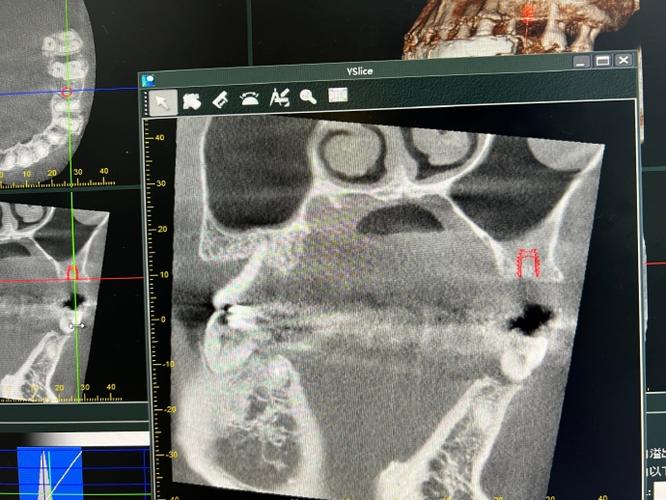

上颌窦是位于上颌骨体内的空腔,与口腔后牙区(尤其是上颌第一磨牙、第二磨牙)关系密切,其底部与牙槽嵴的距离因人而异,正常情况下,上颌窦底与牙槽嵴间距为1-12mm,当牙齿缺失后,牙槽骨会因缺乏咀嚼刺激而逐渐萎缩,导致种植体植入时尖端可能接近甚至穿通上颌窦底,这种情况在种植牙临床中被称为“种植体与上颌窦关系密切”,是上颌后牙区种植需重点规避的风险因素之一。

导致这一情况的原因主要有三方面:先天因素部分患者上颌窦底位置较低(如“牙根突入上颌窦”的解剖变异),或牙槽骨天生较薄;后天因素长期缺牙、牙周病或外力撞击导致牙槽骨萎缩,骨高度不足;手术因素术前影像学评估不充分,未精准测量上颌窦位置,或种植体选择过长、植入角度偏差,导致尖端过度接近窦底。

为规避风险,上颌后牙区种植前必须进行CBCT(锥形束CT)三维评估,明确上颌窦底的形态、位置、黏膜厚度以及剩余牙槽骨的高度与密度,根据骨量情况,制定针对性方案: